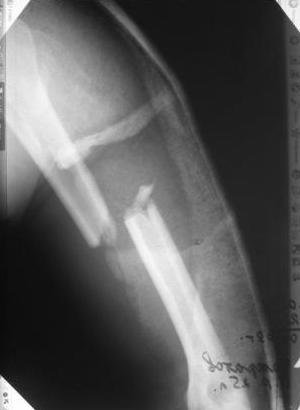

Перелом нестабильный, тактика - если позволяет сосояние больной, оперативное лечение. Как пример см. ниже, можно без скобы - стяжки с ЭПФ.

Представленный способ, функциональный, данная больная в качестве внешней иммобиллизации в течение 3-х недель полльзовалась косыночной повязкой, востановление функции плеча полное. Правда травма изолированная, но операция выполнялась через три недели после травмы, тот час после обращения ко мне - иногородняя.

Да, как раз блокированная пластина и стоит, не синтезовская метадиафизарная, Рыбинская, но на порядок дешевле, а профилактика всех осложнений - в данном конкретном случае, начало ранней на вторые сутки - после удаления дренажа разработки движений в смежных суставах. Если же идти с ревизией т.е. всё равно, открыто как вариант небольших разрезов при поперечном переломе можно и комбинированный мос (см.на вкладыше), хотя думаю для такого способа перелом всётаки низковат.

Всё правильно, просто я несколько разрозненно пытался сказать на частных примерах, то , что Вы систематизировали. Совершенно верно данный перелом можно и так и эдак, наиболее оптимально антеградное штифтование, хотя я бы предпочёл пластину LCP(просто - ну лучше у меня это получается и всё, а больному не вредит тот же функциональный способ). А низковато для неблокированного штифтования с конструкциями с термомеханической памятью, то, что представленно на втором снимке.